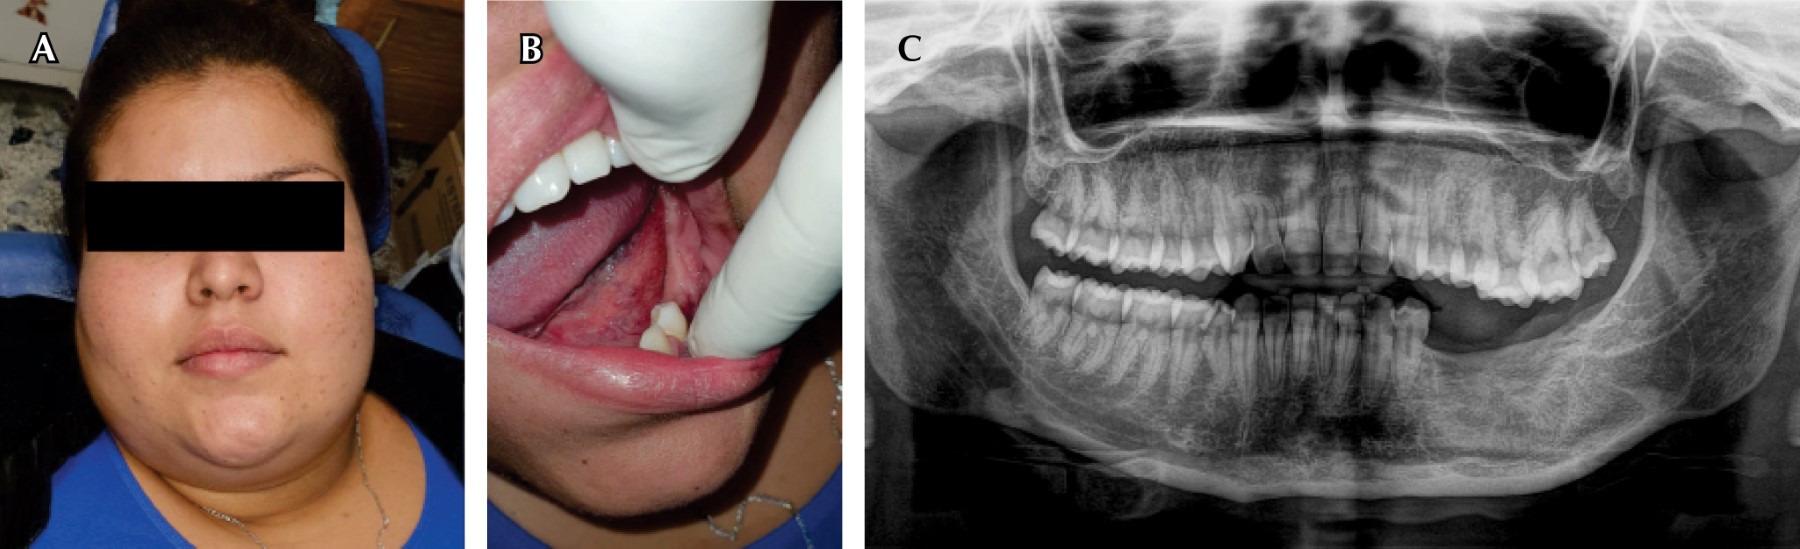

Paciente femenino de 11 años de edad que acudió a consulta en el Departamento de Cirugía Maxilofacial del Hospital Infantil de Morelia, fue referida por el Servicio de Urgencias del mismo nosocomio (Figura 1). Estaba acompañada por su tutora, quien dijo haber notado un incremento de volumen en el cuerpo de la mandíbula de la paciente, del lado izquierdo y que comenzó hacía seis años, por lo que fue tratada de múltiples maneras sin resultados favorables; pero debido a que el incremento era constante, acudieron al hospital. La paciente indicó que se trataba de una lesión asintomática y que únicamente cuando masticaba presentaba una ligera molestia. Además, no tenía antecedentes de importancia para su padecimiento.

Durante la exploración física se observó asimetría facial debido al aumento de volumen en la región submandibular izquierda, de aproximadamente 7 × 4 cm. En la exploración intraoral se presentó pérdida de la línea continua del fondo de saco, por debajo de los órganos dentales posteriores inferiores izquierdos, presencia de tumoración inmóvil, indurada, normocrómica y normotérmica, con presencia de movilidad grado 2 en los dientes 35 y 36. De forma radiográfica se apreció una lesión radiolúcida con bordes radiopacos y expansión de la cortical que abarcaba del órgano dental 35 al 37, así como destrucción radicular del 35 y 36, la lesión involucró la corona del 37 (Figura 1).